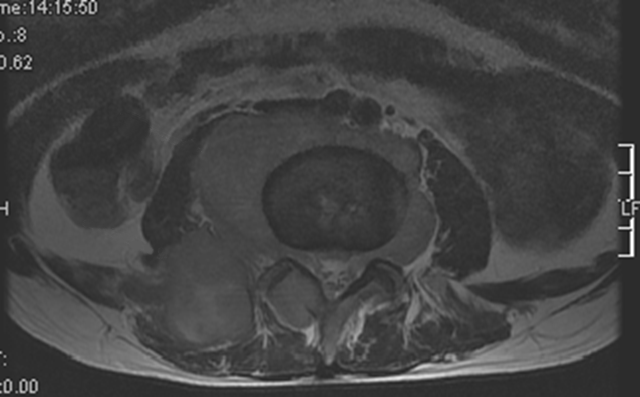

软组织肿块

软组织肿块是诊断恶性骨肿瘤重要依据。X 线平片、CT 及 MRI 均可用于软组织肿块的评估,X 线平片显示软组织肿块作用有限,表现为局部软组织密度增高影,边缘隐约可见(图 55),CT 和 MRI 显示软组织肿块明显优于 X 线平片(图 56、图 57),可清楚显示软组织肿块的大小、边缘轮廓外,还可清晰显示软组织肿块内部病理变化,对肿瘤定性诊断有帮助作用。对于软组织肿块影像学需重点观察其边缘、密度/信号均匀性,是否伴有钙化或骨化,增强扫描后强化特点以及瘤周是否伴发水肿等表现。

图 57.软组织肿块:骨淋巴瘤